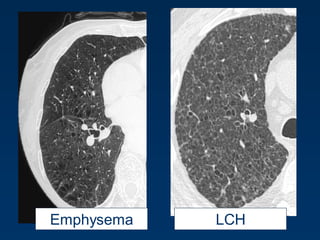

LAMEmphysema Fibrosis

LCHEmphysema

Emphysema typically presents as

areas of low attenuation without

visible walls as a result of

parenchymal destruction.